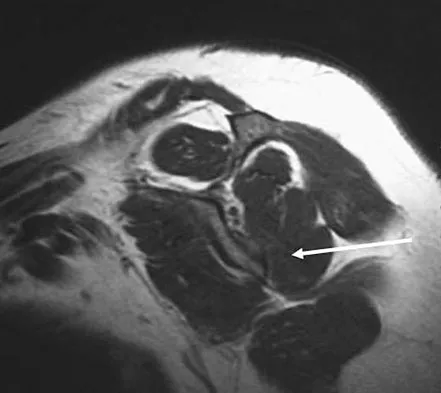

Figure 7 shows a sagittal T1-weighted MRI scan. What muscle/tendon is identified by the arrow?

Explanation

The sagittal T1-weighted MRI scan is useful for interpreting the quality of muscle. The arrow is pointing to the teres minor. Goutallier D, Postel JM, Gleyze P, et al: Influence of cuff muscle fatty degeneration on anatomic and functional outcomes after simple suture of full-thickness tears. J Shoulder Elbow Surg 2003;12:550-554.

References:

- Agur AM (ed): Grant's Atlas of Anatomy, ed 9. Baltimore, MD, Lippincott Williams & Wilkins, 1991, p 394.